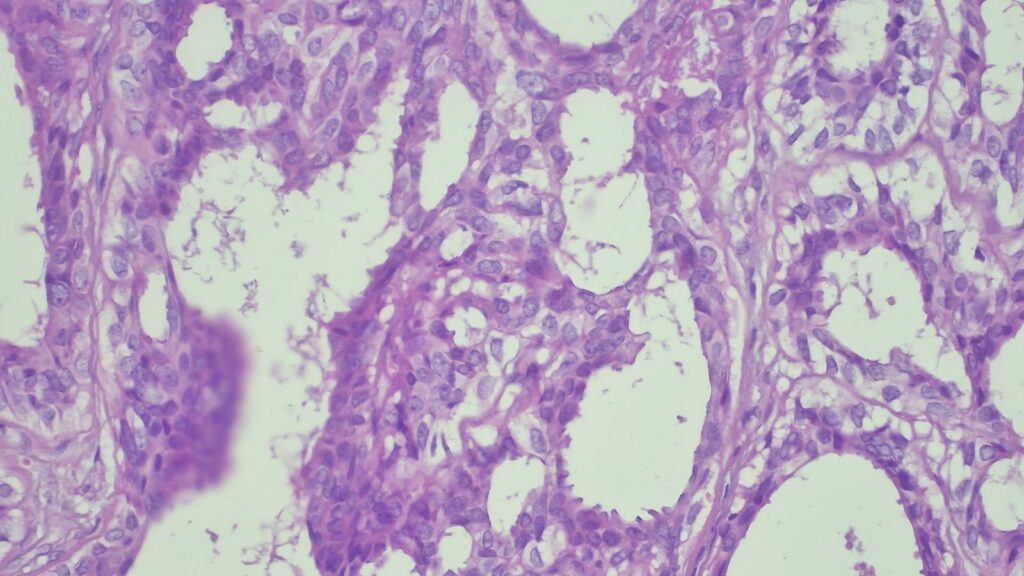

✅ 腺体发育良好,呈圆形和分叶状结构。 ✅ 边缘虽略不规则,但整体呈推挤性(pushing)和局限性生长。 ✅ 无弥漫性浸润结构。 ✅ 无促结缔组织增生性间质反应(No desmoplastic stromal reaction,这是排除浸润癌的核心点)。 ✅ 细胞学形态温和(Bland cytology)。 ✅ 在慢性炎症和纤维化的背景下,仅见单个典型的核分裂象。 在病变外周,腺体表现出被瘢痕样间质压迫和塑形的特征,而不是破坏性或浸润性生长。

CK7: 阳性 (+) CK20: 阴性 (-) p53: 野生型表达模式 Ki-67: 增殖指数极低 🎯 【最终诊断】 综合所有特征,该病变最符合与慢性肛瘘相关的良性/反应性腺体组织,极有可能是被闭塞/嵌顿的肛腺或肛管残余(Entrapped anal gland or duct remnant),而非腺癌!

警惕慢性炎症的“伪装”:慢性肛瘘会将原本正常的肛腺或导管残余包裹,并将其推挤移位至皮下深层组织。这种“异位”在显微镜下极易模仿恶性肿瘤。 鉴别要点速记: 看到圆形、分叶状的结构,更倾向于良性嵌顿。 **缺乏间质促纤维增生反应(Desmoplasia)**是反对浸润癌的强有力证据。 偶尔出现的核分裂象可能是反应性的,不必过度恐慌。 记住一句话:整体结构特征的判断,重于主观的焦虑(Architecture > anxiety)。